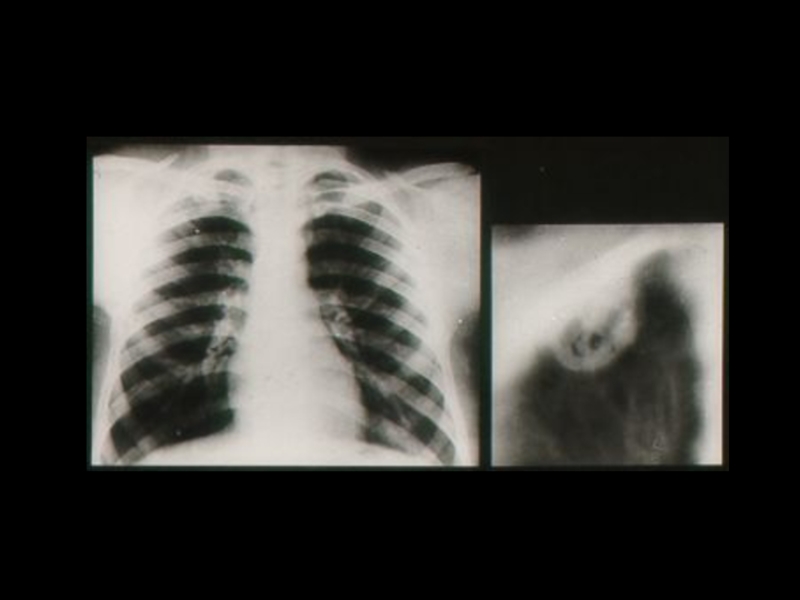

Слайд 18Методы традиционной рентгенодиагностики:

1. Общие методы

(рентгеноскопия, рентгенография)

2. Частные

методы

(флюорография, томография,

электрорентгенография, маммография и

другие)

3. Специальные методы

(урография, бронхография, ангиография,

лимфография, пневмоартрография и другие)

Методы традиционной рентгенодиагностики:1. Общие методы   (рентгеноскопия, рентгенография)2. Частные методы   (флюорография, томография,